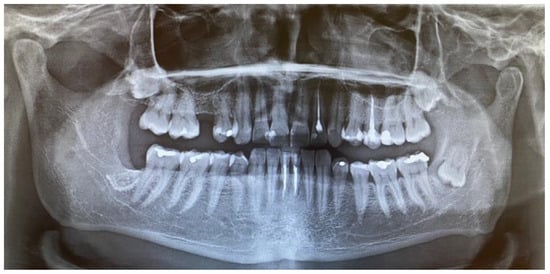

Because of the lack of clear margins after the excisional biopsy and the presence of some of the retained wisdom teeth, a decision was made to radicalise the first procedure. The main focus was to maintain good soft tissue margins, and the remaining wisdom teeth were removed, followed by the use of an osteoalveoplasty procedure. Control CBCT and panx evaluation revealed that the bone and tooth status after the first procedure was good and that the patient had healed properly (Figure 4, Figure 5 and Figure 6).

Figure 6. A routine panoramic (panx) radiograph one year after revision surgery and extended radical removal of the schwannoma. Kinking of the inferior alveolar nerve canal is visible along with the remnants of the impacted third molar crown.